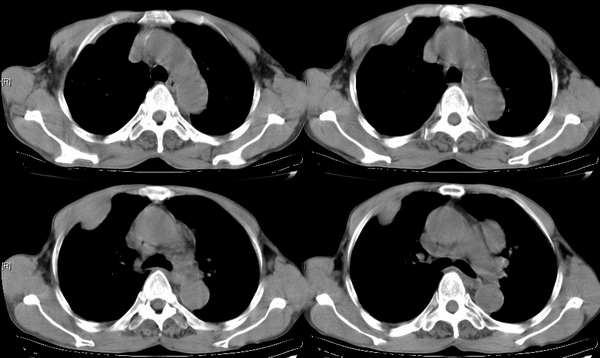

右颈部巨大软组织肿块影,范围较广,上至下颌角,下至颈静脉切迹。其最大层面位于右侧甲状腺区。肿块密度不均,其中有坏死液化区和班片状钙影,增强扫描见肿块实质区有强化。邻近结构挤压移位,部分结构侵蚀破坏,右侧多个颈深淋巴结肿大。两肺弥漫分布小结节影,以胸膜下为主,其大小不等,边缘光整。右侧胸壁亦见软组织结节影,纵隔多个淋巴结肿大及两侧锁骨上淋巴结肿大。

意见:右侧甲状腺癌并两肺、胸壁、纵隔淋巴结、颈深淋巴结、锁骨上淋巴结等广泛转移。

右侧甲状腺腺癌伴颈部纵隔淋巴结转移、纵隔淋巴结转移、肺内多发转移及胸膜转移。

典型,肺部转移瘤

右侧甲状腺癌伴两肺多发转移、纵隔淋巴结转移及胸膜转移